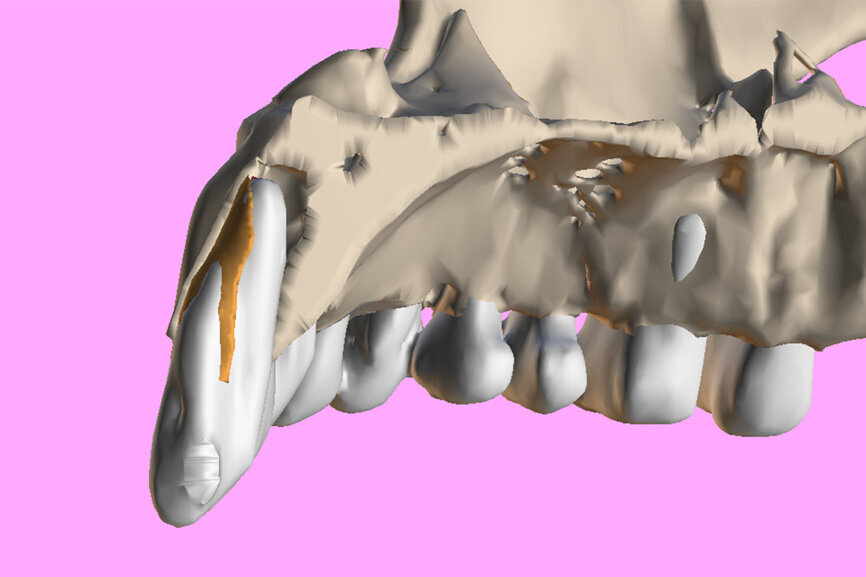

Fig. 4: The segmented root (white) and the root fragment (brown) within the sectioned maxillary surface model.

One indication for PET is when a patient presents with a horizontally fractured clinical crown (Fig. 1). While a 2D radiograph will reveal the extent of the horizontal fracture, length of the remaining root and approximation of the bone apical to the root, there is not enough information to plan for a PET procedure. A CBCT scan is recommended in order to fully appreciate the root position within the alveolus and the potential difference between the trajectory of the bone and the trajectory of the root as can be visualised with a cross-sectional image (Fig. 2). Utilising interactive treatment planning software makes it possible to plan the initial drill path to accurately section the root to its apex (Fig. 3a). This can be accomplished by creating a custom implant design to match the diameter of the initial drill with an abutment projection in order to fully appreciate the trajectory through the clinical crown (Blue Sky Plan, Blue Sky Bio). It is important to visualise the root fragment that will remain in order to properly simulate the position of the implant in the alveolus (Fig. 3b). The apical portion of the implant can be positioned to gain stability in host bone using the Triangle of Bone. It is important to note that a cross-sectional slice may only be 0.125 mm in thickness based on the CBCT acquisition, and therefore all images in all views must be visualised to confirm the plan. Utilising 3D segmentation (separating objects by density values), it is possible to define each root and further assess the simulated position of the implant with a sagittal cut through the 3D reconstructed volume (Fig. 4).

The ability to export volumes in STL format allows these objects to be edited and utilised in other software applications, such as Meshmixer (Autodesk). The STL file of the root image was imported into Meshmixer, and the root was virtually sectioned using Boolean difference to mimic the crescent shape for PET (Fig. 5a). The apical portion of the simulated implant can then be positioned so as not to touch the root fragment while engaging in host bone for stability (Fig. 5b).